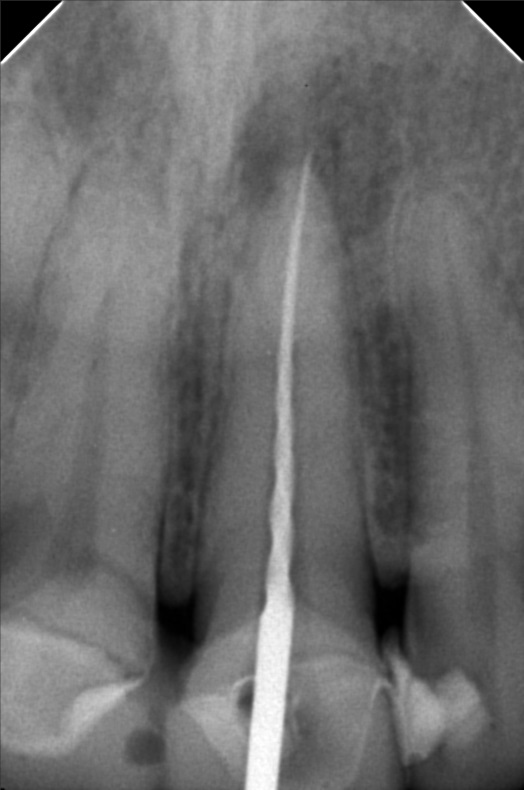

- 01/31/21 OP xray 11&21 #21 with periapical abcess 02/07/25 White and Yellow file patent 25mm apexcal ICF

- yu_2.jpg